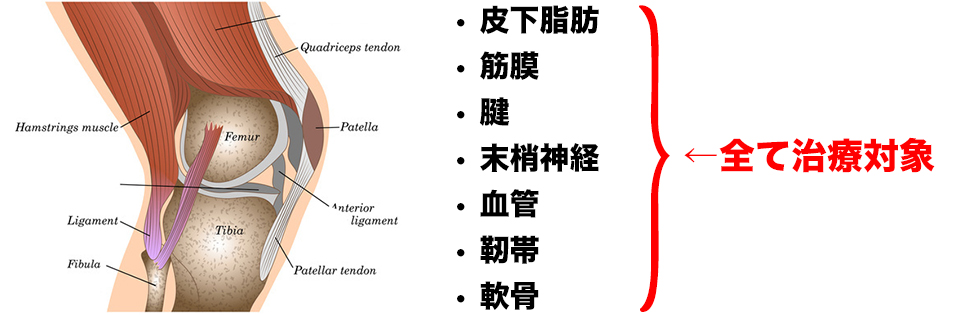

例えば、靭帯に何か原因があるかもしれないと思っても、実際、靭帯にアプローチできる理学療法士は皆無に等しいですし、わかったとしても使いこなせないことがほとんどだと思います。このセッションでは、血管や靭帯などにある原因を素早く見つけ出し、効率良くリリースして、痛みを改善できる3ステップを実例を交えながら詳しくお伝えします。そして、この「3ステップ」は、たとえ臨床1年目の新人だろうが、20年以上の超ベテランだろうが、同じ結果を出すことができます。

筋膜や皮下脂肪、靭帯、腱、関節包、そして血管や神経を取り巻く結合組織のことを結合組織(fascia)といいます。そして、エコーで筋膜を撮影すればその奥にある血管や皮下脂肪、靭帯、腱、関節包、関節軟骨、神経、も映し出すことができます。そして研究時に対象の筋膜をリリースした後に、もう一度撮影すると明らかに筋膜以外の組織も緩んでいることが判明しました。

変形性膝関節症、肩関節周囲炎、大腿骨頸部骨折、坐骨神経痛、脊柱管狭窄症など筋膜リリースだけでは、その場での改善できず、時間が経つごとに患者さんの自然治癒力で徐々に治っていく様を見て「よかったね」と言うしかなかった、そんな痛みに対しても結合組織をリリースできれば改善することができます。